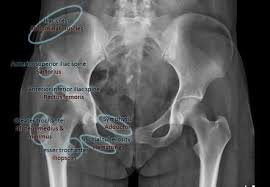

Pelvic Avulsion Fracture Symptoms Causes And Treatment from www.sportsinjuryclinic.net In the pelvis, the newly formed secondary centers of ossification, the apophyses, are the most likely portions of the bone to avulse. In adults, the ligaments and tendons tend to be injured first, whereas in children the bone may fail before. Physical therapy may also help a fracture heal more quickly than immobilization alone. Pelvis injuries range from the benign to life threatening. Your doctor might recommend that you use crutches to keep weight off the hip while it heals. Avulsion fractures are more common in children than in adults. Your doctor might recommend that you use crutches to keep weight off the hip while it heals. Aiis and ischial tuberosity fractures are at increased risk of developing future pain and nonunions, respectively.

They include pelvic ring fractures, acetabular fractures, and avulsion injuries. Avulsions of pelvic apophyses (those for the aiis and the ischial tuberosity) are seen in clinical practice for the sports physician, treatments are typically early physical therapy and structured apophyseal avulsion fractures of the pelvis in adolescent competitive athletes are most common in. Popping or snapping sensation coinciding with physical exertion. An avulsion fracture is when a tendon or ligament pulls a piece of fractured bone away. Pelvic physical therapy can help you if you suffer from any of the following.

Avulsion Fractures Of The Pelvis In Adolescents Eurorad from www.eurorad.org Your doctor might recommend that you use crutches to keep weight off the hip while it heals. An avulsion fracture is an injury to the bone in a location where a tendon or ligament attaches to the bone. When a small piece of the bone breaks off the main bone. Apophyseal avulsion fractures are usually the result of a sudden forceful concentric or eccentric contraction of the muscle attached to the apophysis. In the pelvis, the newly formed secondary centers of ossification, the apophyses, are the most likely portions of the bone to avulse. Your physical therapist will show you how to perform exercises that strengthen the bone and improve your range of motion. They usually happen when a bone is moving one way, and a tendon or ligament is suddenly pulled the opposite way. How good is recovery after pelvic fracture?

Physical exam should not be used to rule out a pelvic fracture in unconscious patients, but it can nearly definitively rule it in. Severe pelvic fractures can be fatal due to internal bleeding or damage to nearby organs, or result in chronic pain and physical disabilities. Exercise increases blood flow, which delivers more. They are not associated with avulsion fractures or stress fractures. Apophyseal avulsion fractures are usually the result of a sudden forceful concentric or eccentric contraction of the muscle attached to the apophysis. Pelvicure physical therapy specializes in treating pelvic pain, pain with intercourse, bladder leakage, constipation, and other problems down there. Like other pediatric fractures, apophyseal avulsion fractures fail through the physis.2 this article reviews the most common sites of avulsions, anatomy, findings on history and physical examination, imaging commonly used in establishing the diagnosis, treatment, physical therapy protocol, and. Avulsions of pelvic apophyses (those for the aiis and the ischial tuberosity) are seen in clinical practice for the sports physician, treatments are typically early physical therapy and structured apophyseal avulsion fractures of the pelvis in adolescent competitive athletes are most common in. Most often, this occurs during sudden movements and changes in direction. In the pelvis, the newly formed secondary centers of ossification, the apophyses, are the most likely portions of the bone to avulse. Aiis and ischial tuberosity fractures are at increased risk of developing future pain and nonunions, respectively. Pelvic fracture is a disruption of the bony structures of the pelvis, including pelvic ring fractures, acetabular fractures, and avulsion fractures. Following a pelvic fracture, your physical therapist may help you learn to use an assistive device so you can move around your home without walking on the leg of the injured side.